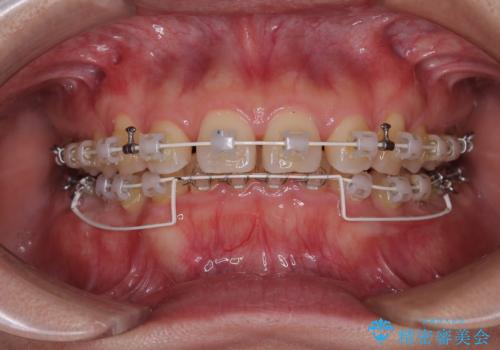

- 審美装置

咬合力が強いことと、マウスピースを長時間装着する自信がないとのことで、ワイヤー装置にて矯正治療を行うこととしました。

下顎臼歯を起き上がらせるためにユーティリティーアーチを使用し、一気に深い咬み合わせを改善することができました。